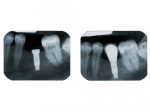

- Un implant dentaire est une racine artificielle placée par le chirurgien-dentiste dans l'os alvéolaire de l'un des maxillaires en remplacement de la racine d'une dent extraite et servant de support à une prothèse.

Sa forme est généralement cylindrique ou légèrement conique, ressemblant à une vis, en titane ou en zircone, avec une connexion au niveau supérieur, à l'emplacement de la gencive, pour permettre la pose d'un élément prothétique par vissage ou scellement.

Son diamètre varie entre 3 et 5mm et sa longueur entre 8 et 15mm.